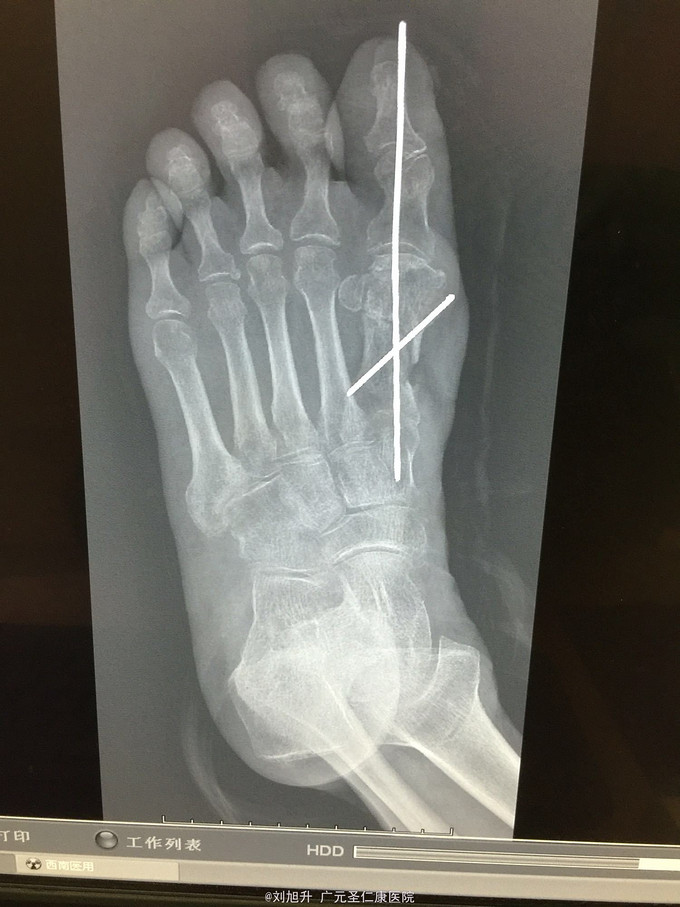

左足背砸伤

患者,男,61岁,因左足背重物砸伤5小时入院